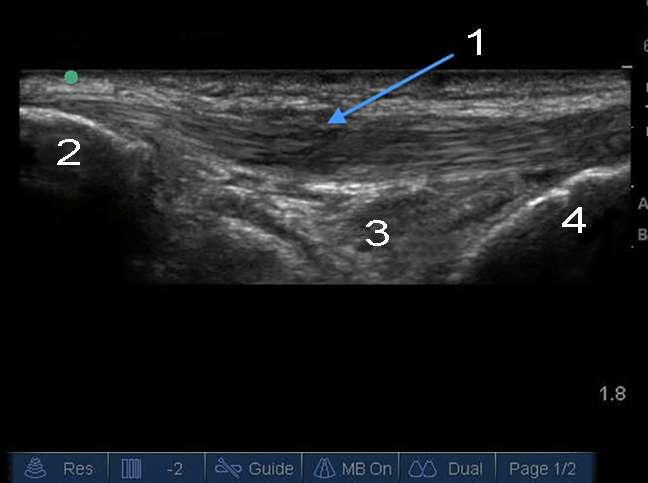

Imagen de tendinosis infrarrotuliana de la rodilla

1. Engrosamiento de tendón rotuliano longitudinal

2. Rótula

3. Almohadilla grasa de Hoffa

4. Tibia